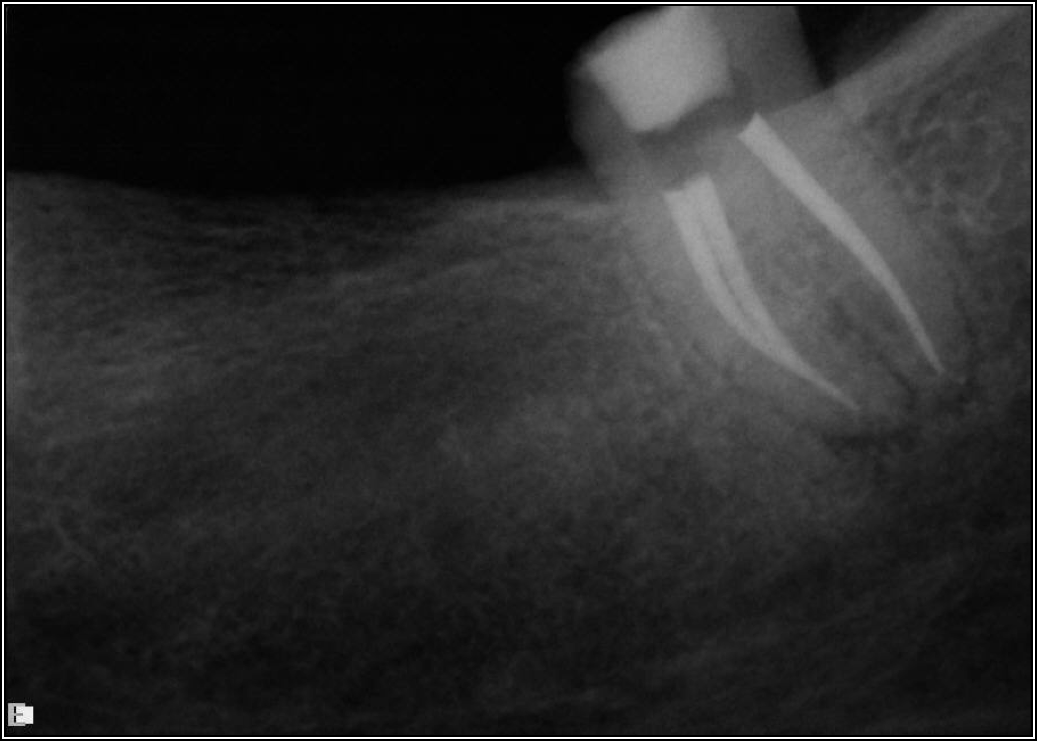

Fig 2. Minimal walls.

Figure 2

Figure 2 shows a situation where the clinician excavated the tooth of a patient with decay, and it pulped out. The buccal and lingual walls were intact; however, the walls were minimal, and there were still fragments of amalgam and cracks. If the clinician prepared this tooth after building it up, the clinician would lose all the good tooth structure that was left. This tooth would likely need a post.